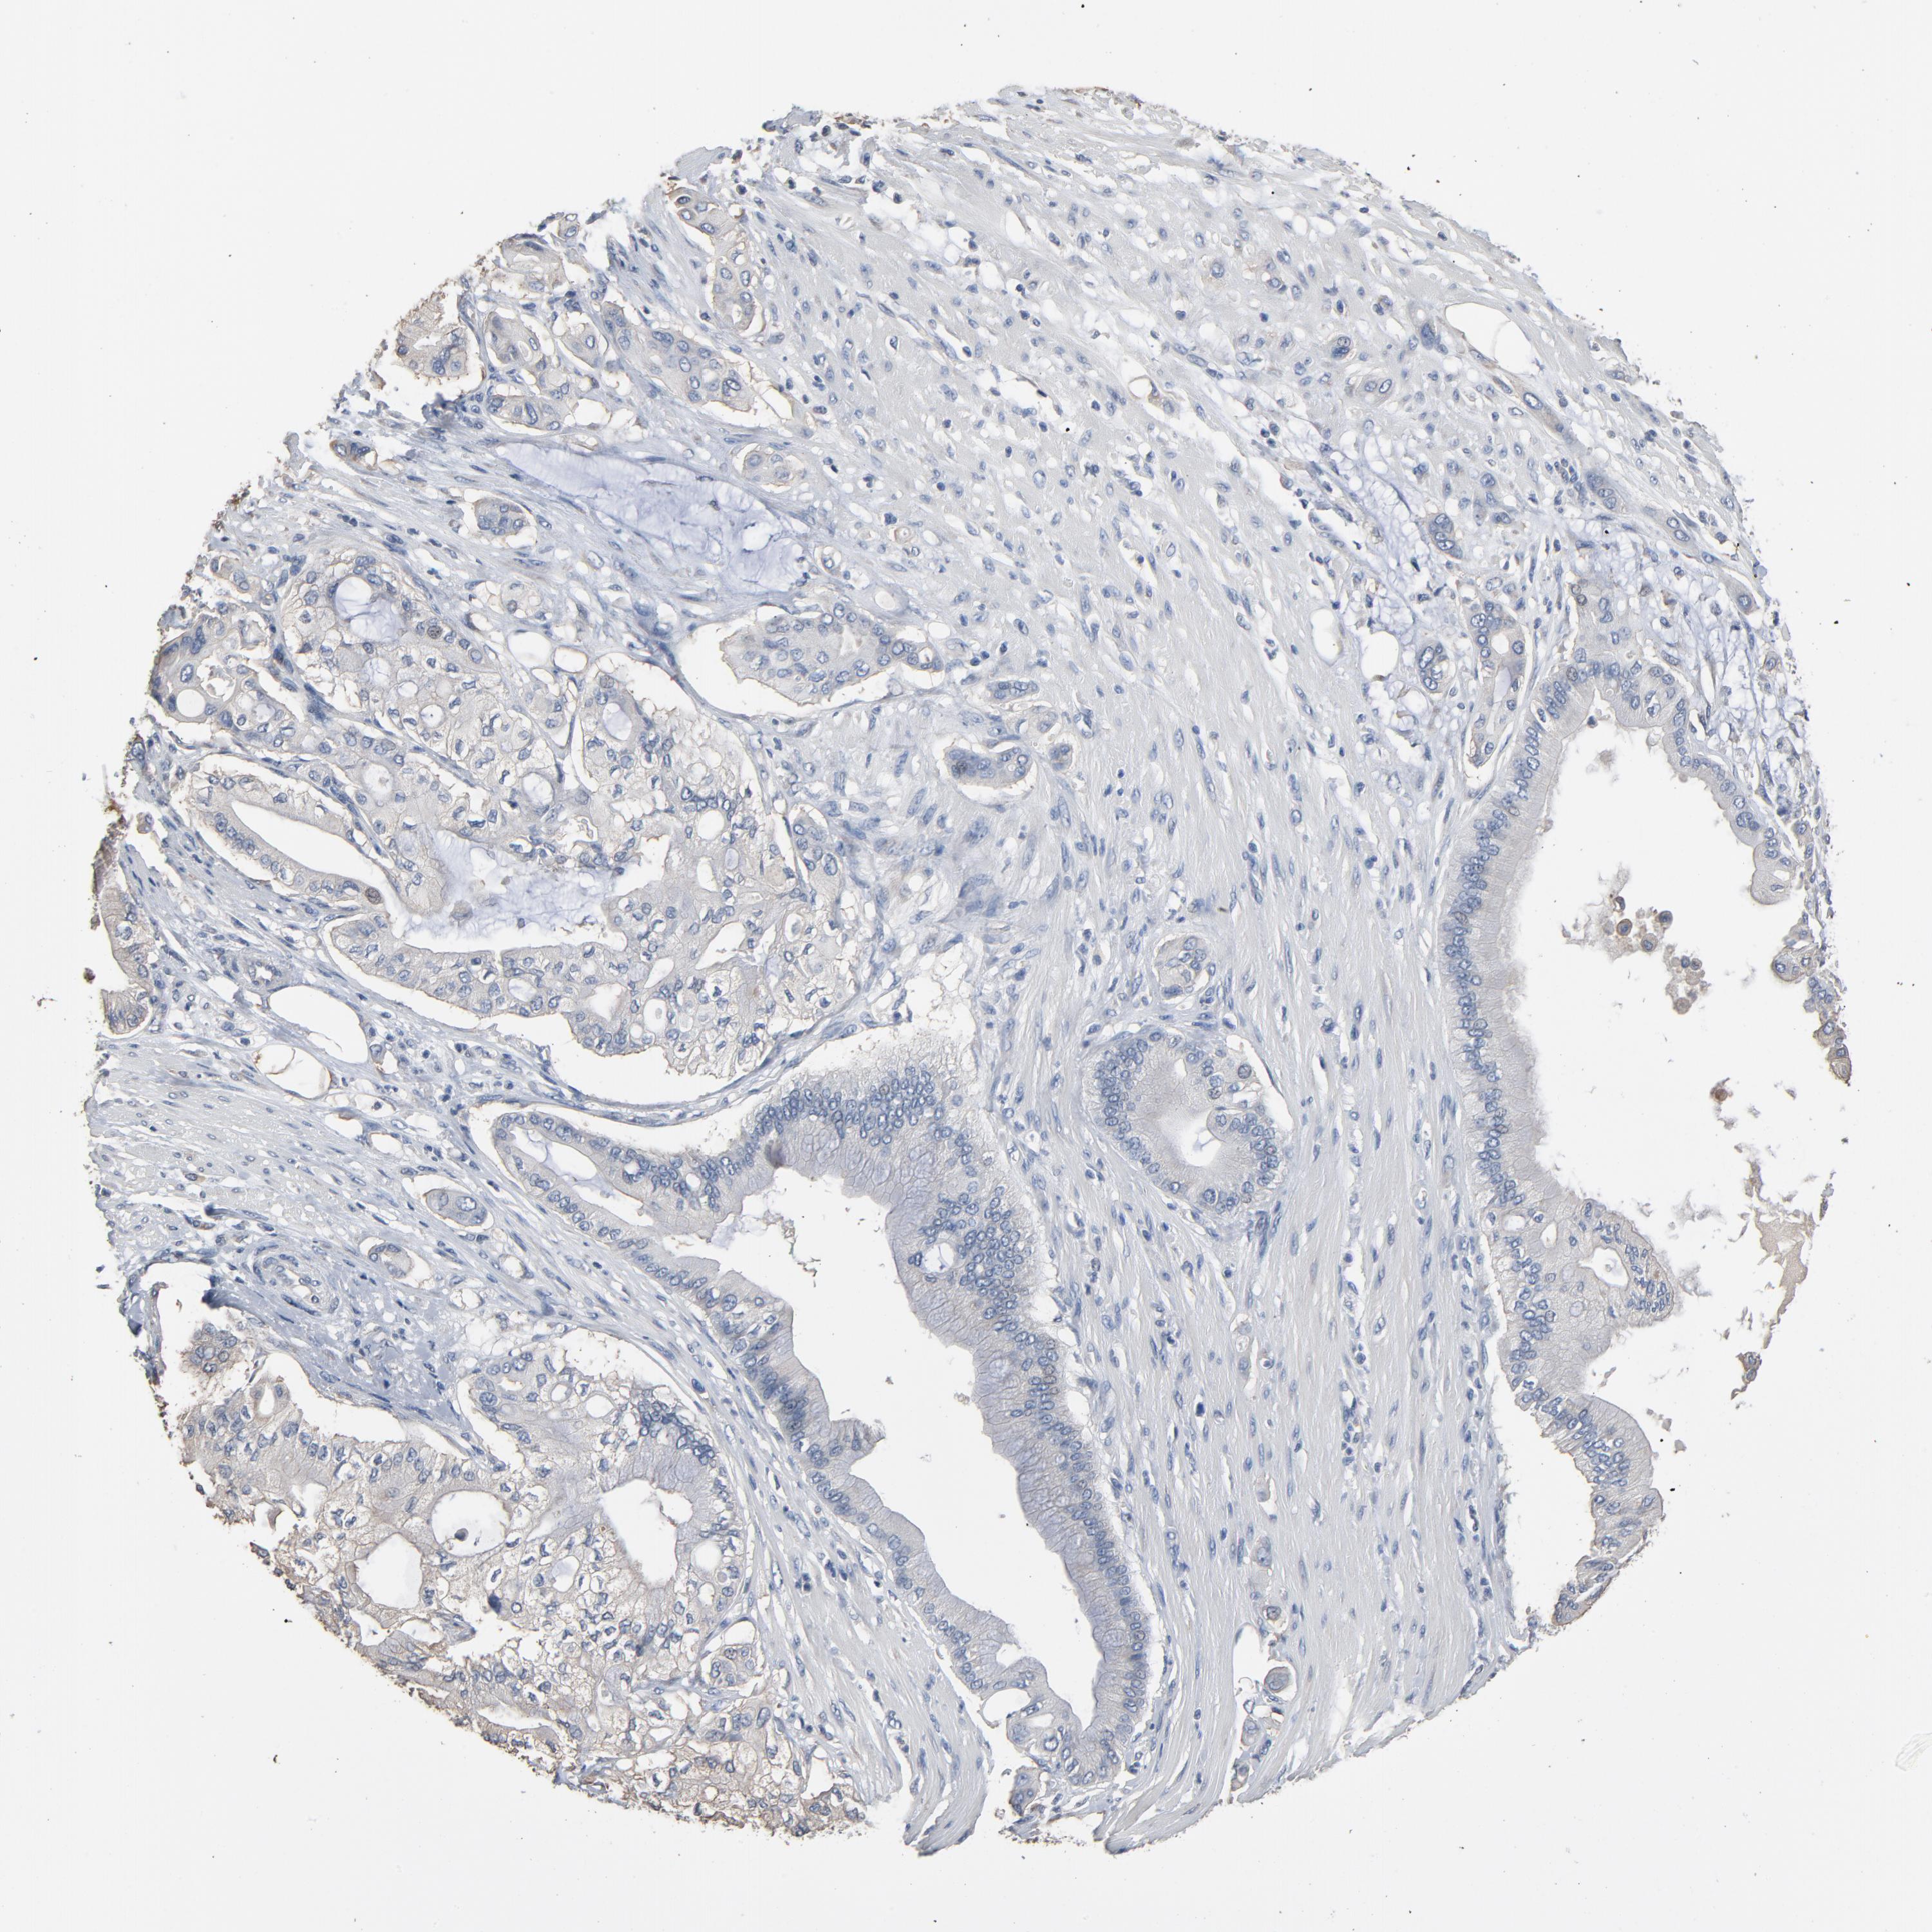

PANCREATIC CANCER - Protein expressioni

A mouse-over function shows sample information and annotation data. Click on an image to view it in a full screen mode. Samples can be filtered based on level of antibody staining by selecting one or several of the following categories: high, medium, low and not detected. The assay and annotation is described here.

Note that samples used for immunohistochemistry by the Human Protein Atlas do not correspond to samples in the TCGA dataset.

Antibody stainingi

Antibody staining in the annotated cell types in the current human tissue is reported as not detected, low, medium, or high, based on conventional immunohistochemistry profiling in selected tissues. This score is based on the combination of the staining intensity and fraction of stained cells.

Each image is clickable and will lead to virtual microscopy that enables deeper exploration of all samples and also displays staining intensity scores, fraction scores and subcellular localization as well as patient and tissue information for each sample.

Antibody HPA001923

Antibody HPA003908

Adenocarcinoma, NOS

Adenocarcinoma, metastatic, NOS